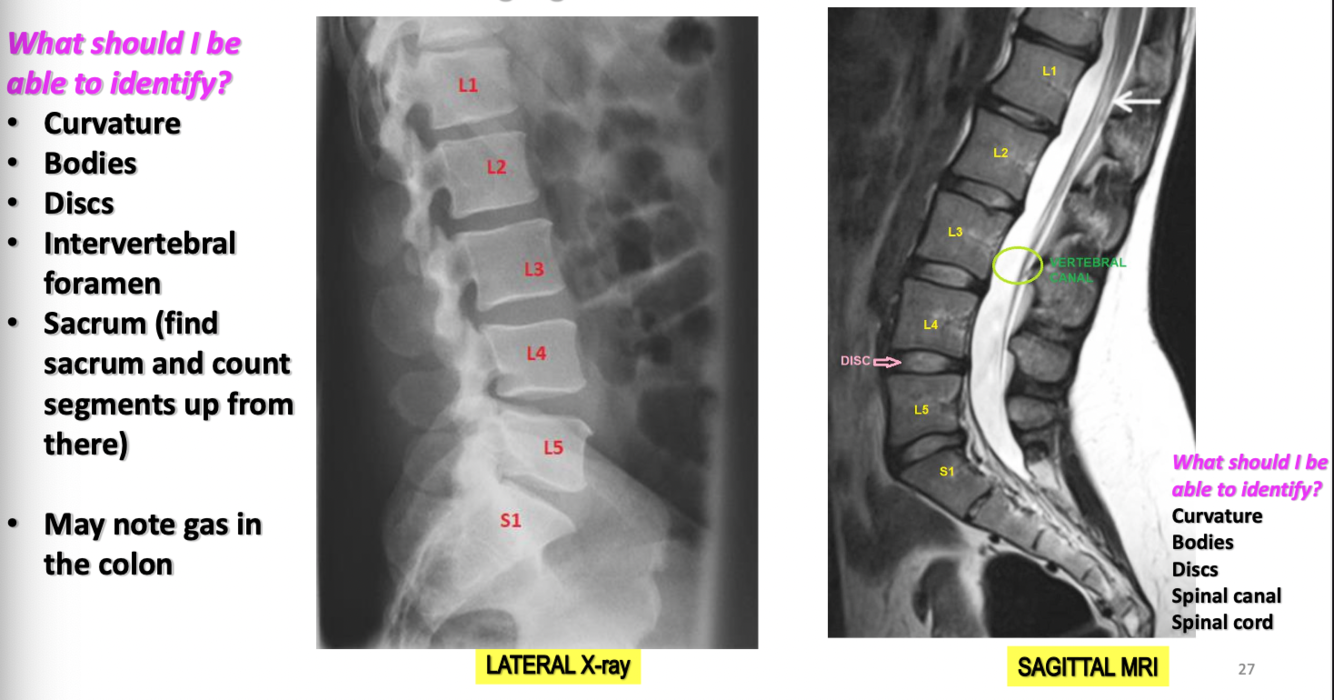

Imaging of Lumbar Vertebrae

22